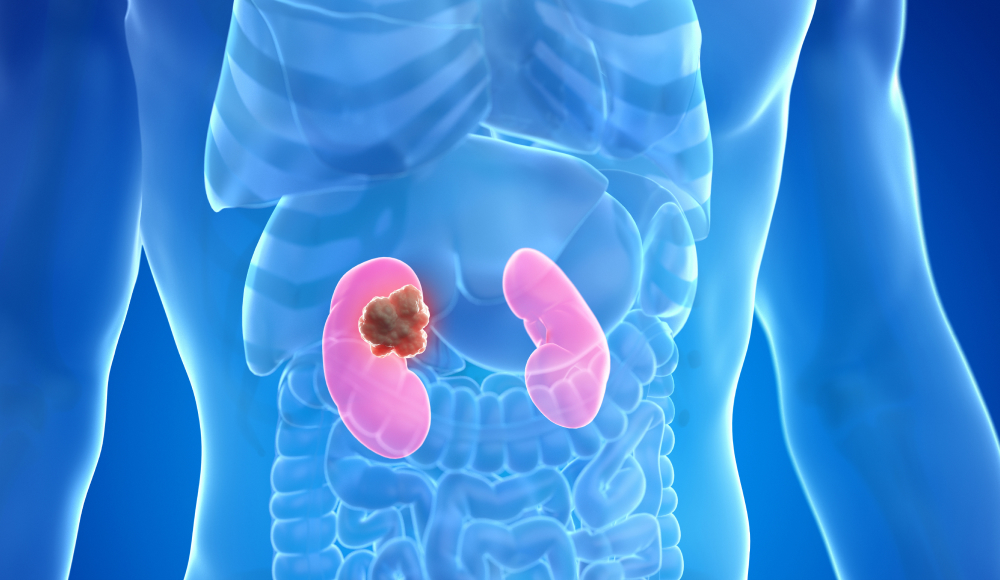

It’s Advanced! 경피적 신장결석 제거술,

골드만이 앞서가는 이유 BIG 5

전날 입원, 전신마취, 긴 회복 기간? 골드만에서는 모두 NO!

환자 중심으로 설계된 새로운 PCNL 시스템을 경험하세요.